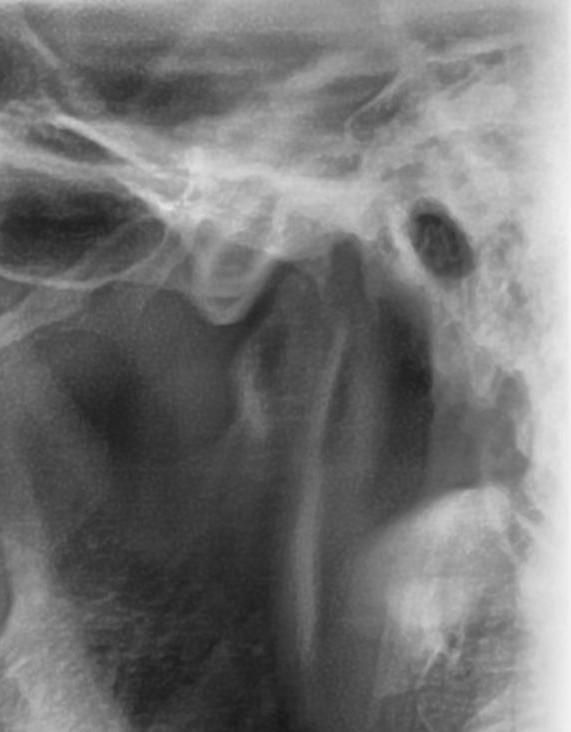

턱 관절 과두 상태 전 후 상태 한 번 봐주세요

최근에 턱 관절 통증 때문에 사진을 한 번 찍어 봤는데요 예전 사진과 비교 했을 때 어떤지 한 번 봐주시겠어요?

사진1,2가 전이고 3,4가 후 입니다

엑스레이 상으로도 턱관절이 좋아 보이진 않습니다. 일단 구강내과를 가셔서 턱관절 정밀검사를 받아보시고 치료를 받으시는게 좋을것같습니다.

파노라마 사진으로는 턱관절을 정확하게 진단하기는 어렵습니다. 과두부분이 평평하게 되어있는 모양으로 유추해 봤을때 과두에 강한힘이 오래동안 작용했을수 있습니다. 턱관절질환은 턱관절에 가해지는 힘이 강해서 생기기 때문에 턱관절에 가해지는 힘을 줄이는것이 좋습니다.